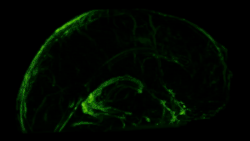

In transgenic mice containing Prox1-GFP or Vegfr3-LacZ reporter genes, the lymphatic vessels may be visualized by fluorescent microscopy or after X-gal staining, respectively.[2]

To visualize the dura mater using immunohistochemistry, the dura must first be fixed within the skullcap. It is prepared by cutting around the base of the skull (inferior to the post-tympanic hook) and removing the lower portion of the skull and brain. Following fixation, the dura can be dissected out of the skullcap as a single piece of tissue that can be utilized for histological analysis.[12]